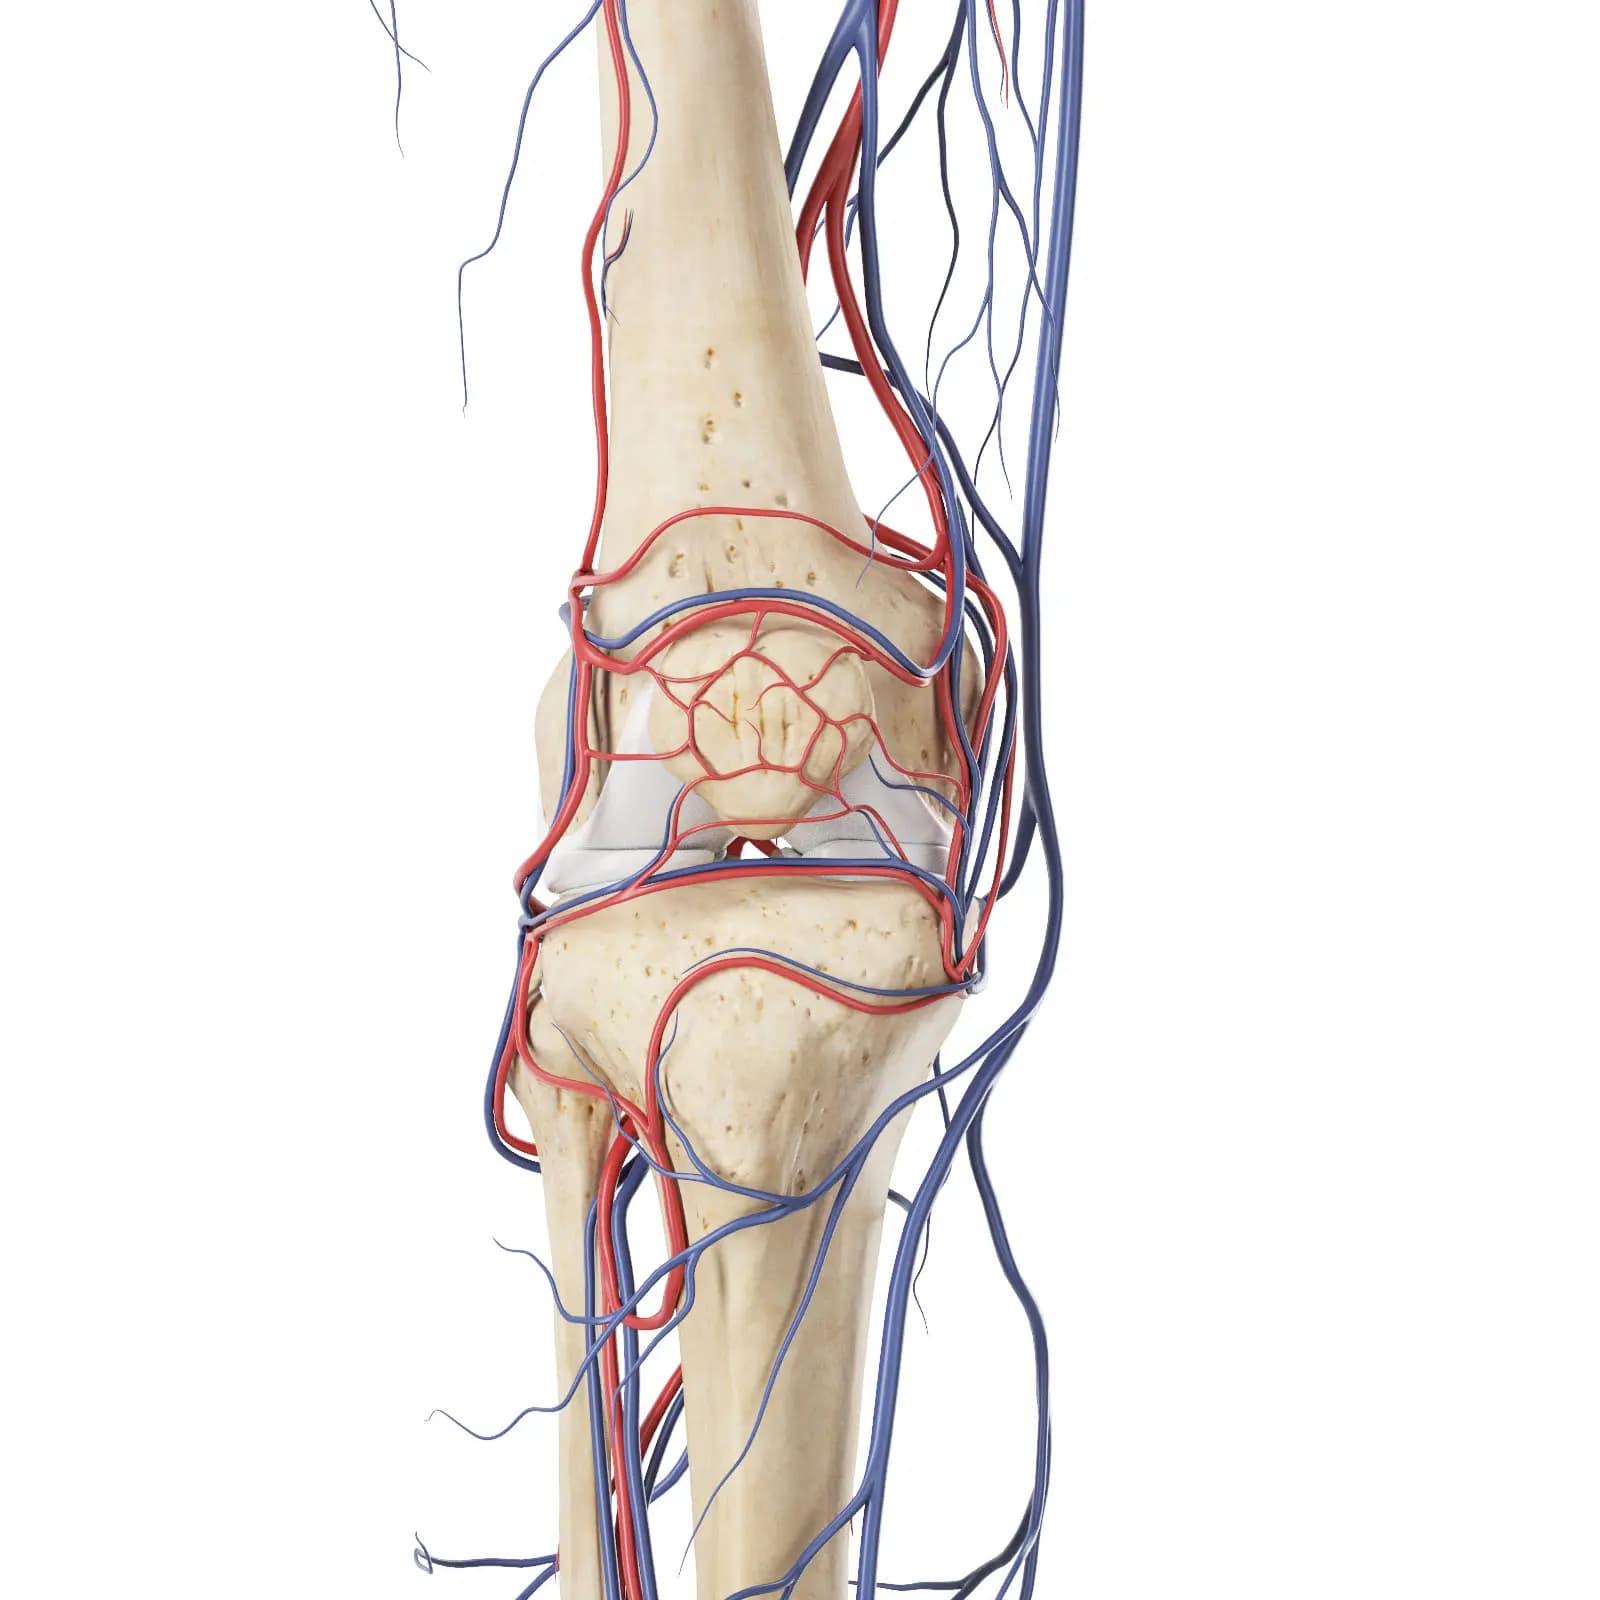

3d Rendered Medical Illustration Of The Vascular System Of The Knee

3d Rendered Medical Illustration Of The Vascular System Of The Knee